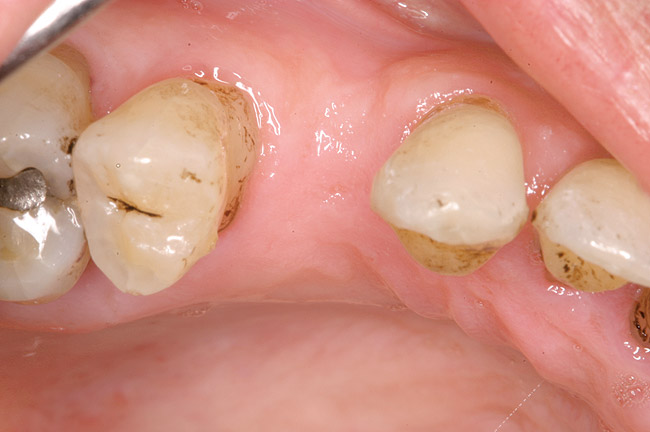

In this example, the more predictable option would have been to place an implant in the No. 30 position and restore the area as three single units. However, the treatment delivered involved a four-unit fixed bridge, which then included tooth No. 28. Unfortunately, this bridge failed at approximately 5 years (Figure 7 and Figure 8) because of a root fracture of tooth No. 29 and advanced furcation involvement with residual endodontic infection of tooth No. 30. The inclusion of tooth No. 28 into the bridge also decreased its long-term prognosis because of its preparation.43 The alternative restorative option of a RPD also would decrease the prognosis of the RPD abutment teeth, which fail more often than FPD abutment teeth.43

Figure 7  Condition of the teeth seen in Figure 6, approximately 5 years after restoration. Note the extensive furcation involvement of tooth No. 31 and its residual periapical radiolucency.

Figure 7

Figure 8  Same case as in Figure 7 showing teeth Nos. 28 and 29. Note that tooth No. 28 was included into the four-unit restoration, and the small radiolucency on the distal tooth No. 29, which was associated with a root fracture.

Figure 8